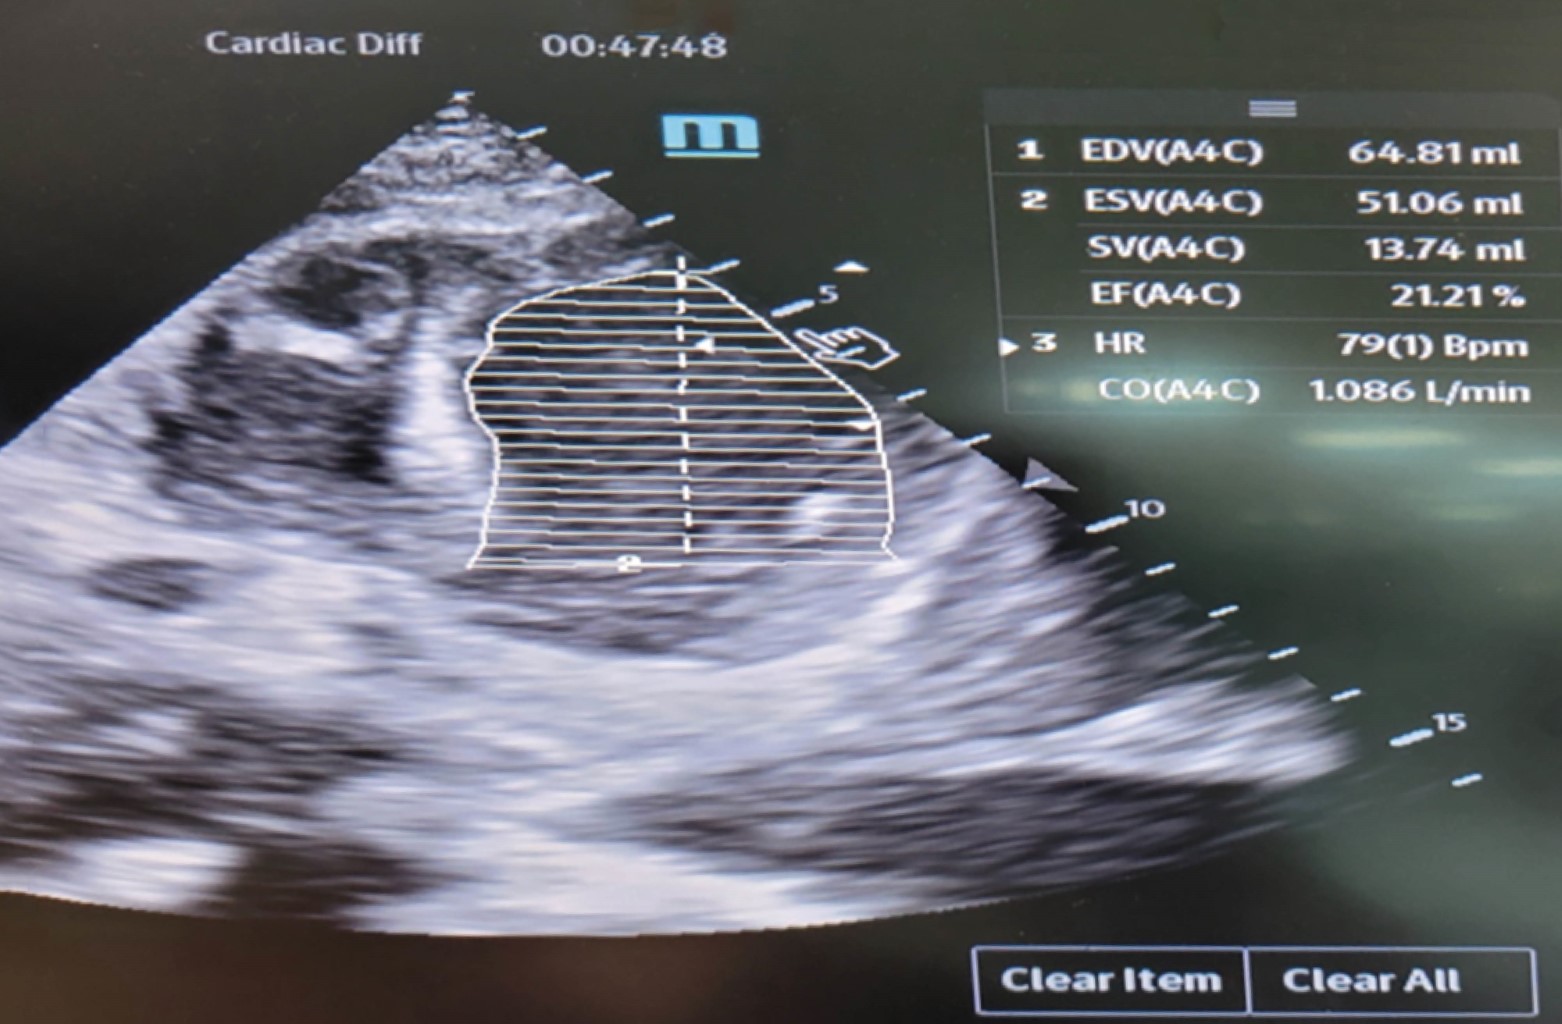

Tako-tsubo syndrome in older adults

Tako-tsubo syndrome is characterized by transient regional systolic dysfunction, mainly of the left ventricle, which can be confused with an acute myocardial infarction. Still, without angiographic evidence of obstructive coronary artery disease, it is triggered by a stress episode. Its highest incidence is in postmenopausal women; in men over 70 years old, it is rare and has higher mortality.

Figure 1